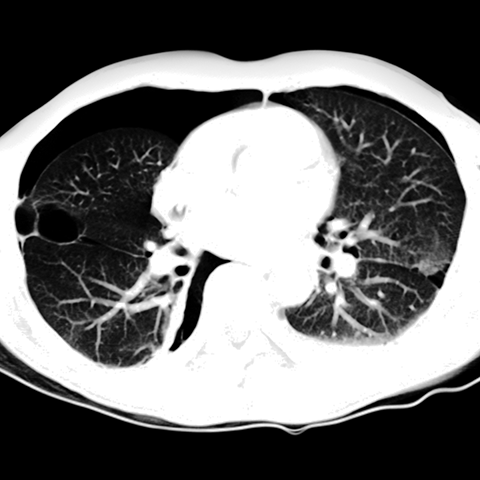

Pneumothorax [2 of 2]